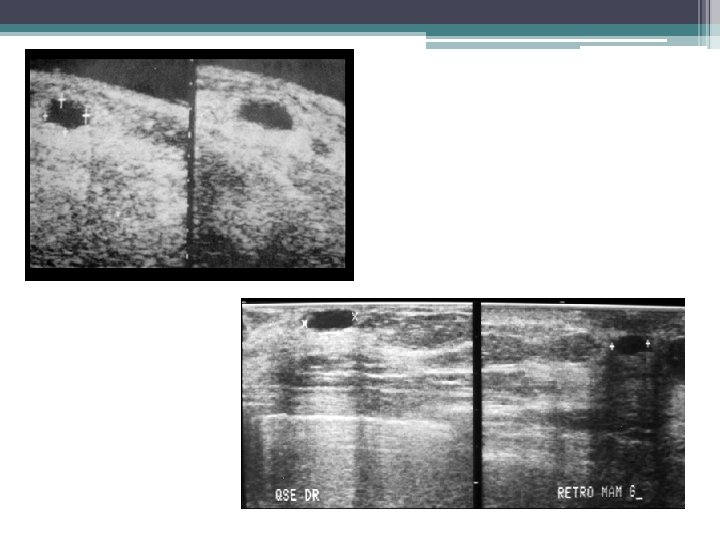

KYSTE DU SEIN • ECHOGRAPHIE: examen clé ▫ Aspect typique: �lacune transonore, à limites nettes, sans ou avec paroi fine régulière. �net renforcement postérieur ▫ Aspect atypique: �liquide épais, paroi épaisse, végétations internes, cloisons �diagnostic différentiel avec : �Adénofibrome, hématome, abcès �Cancer du sein

ADENOFIBROME ECHOGRAPHIE: • Forme typique: ▫ Nodule ovale à grand axe transversal ▫ Contours nets et réguliers. ▫ Hypoéchogène homogène avec renforcement postérieur, cônes d’ombre latéraux ▫ Mobile et compressible sous la sonde • Les formes atypiques sont fréquentes: ▫ lésions solides ne réunissant pas tous les critères de bénignité ▫ atténuation post (composante fibreuse et/ou calcique).